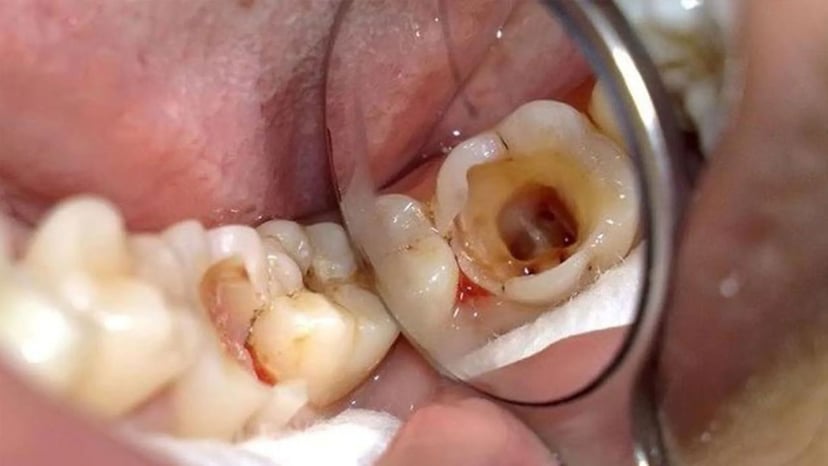

– Các bệnh viêm lợi ở trẻ khi xảy ra còn tiềm ẩn nguy cơ gây hại đến chất lượng men răng, khiến răng bé thường có màu ngà và dễ bị sâu răng hơn trẻ khác.